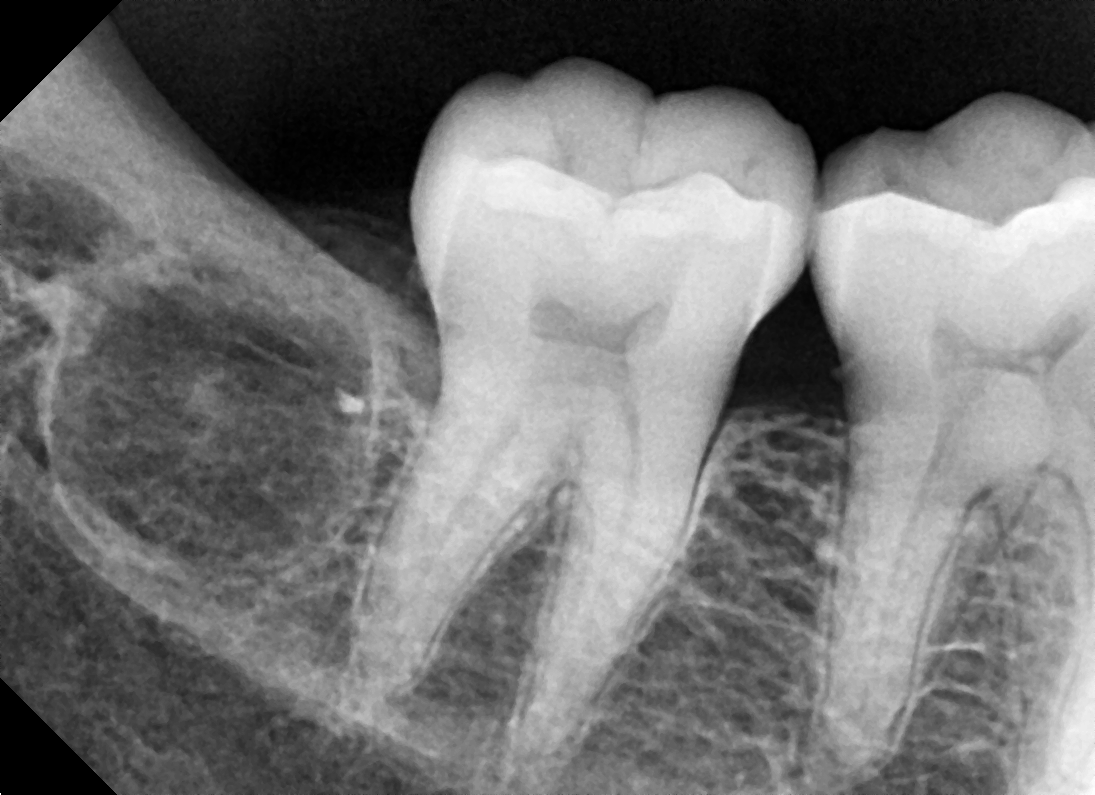

Disto Angular

After After

Before Before